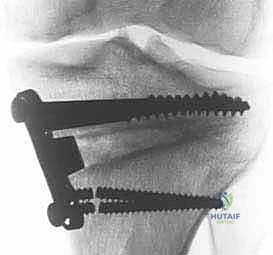

باستخدام أدوات دقيقة ومناشير جراحية متطورة، يتم عمل قطع غير مكتمل في عظمة الساق. هناك طريقتان رئيسيتان:

* الشق المفتوح (Opening Wedge): يتم فتح العظم من الداخل وإضافة طعم عظمي (صناعي أو طبيعي) لملء الفراغ وتعديل الزاوية. وهي الطريقة الأكثر شيوعاً حالياً.

* الشق المغلق (Closing Wedge): يتم إزالة إسفين (مثلث) صغير من العظم من الجهة الخارجية وإغلاق الفراغ.

4. تعديل المحور:

يتم فتح العظم تدريجياً وببطء شديد حتى الوصول إلى الزاوية التي تم حسابها في التخطيط الرقمي قبل الجراحة.